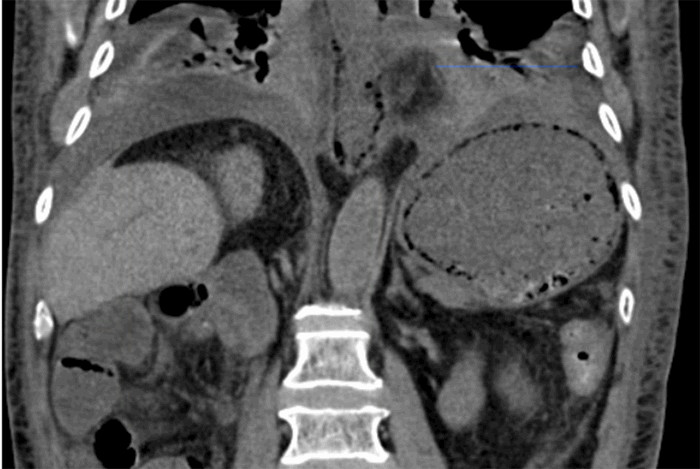

Following this procedure, the patient recovered well; however, on hospital day 14, the patient once again developed nausea, emesis, and hypotension. The decision was made to transfer to the surgical intensive care unit (SICU). Non-contrast CT at this time demonstrated severe pneumatosis of the stomach and esophagus without perforation and without an obvious etiology (Figure 2). Arterial lactic acid slightly elevated to 1.4 mmol/L (normal 0.4-1.3). Conservative management was selected since a surgical approach would have yielded a highly morbid procedure in an already frail patient. In the SICU, the patient received nasogastric decompression of his stomach, support with vasopressors, fluid resuscitation, and antimicrobial agents (vancomycin, piperacillin/tazobactam, micafungin).

Figure 3. CT image, coronal view demonstrating pneumatosis of the stomach and esophagus.